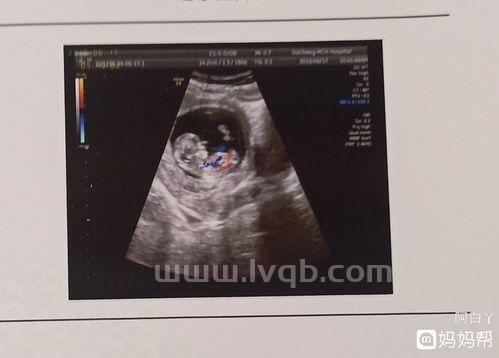

1、b超有两点基本是男孩 看亮点和白线分辨男孩女孩 在做b超的时候如果有幸看到胎儿腿部间有两个或者三个亮点的话,基本怀的就是男孩,如果b超时看到是三条白线,大多数怀的是女孩。

5、b超有两点基本是男孩 b超有两点基本是男孩,主要是宝宝双腿之间生殖器官那里的显示。在做b超的时候如果看到胎儿腿部间有两个或者三个亮点的话,基本怀的就是男孩,如果b超时看到是三条白线,大多数怀的是女孩。